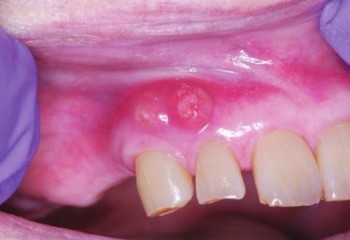

Un abces periodontal se prezinta adesea cu toate semnele unei inflamatii acute locale si infectii: debut abrupt, tumefiere gingivala sau mucosala sau ambele, eritem intens al tesuturilor afectate si durere. Dintre acestea durerea este prima observata si mai ales de catre pacient, care nu recunoaste restul semnelor.

Durerea poate varia de la sensibilitate usoara la percutie, palpare sau severa, spontana, iradiind. Pacientul poate observa ca dintele afectat este mobil, inaltat in ocluzie sau ambele. Tesuturile afectate sunt albastrui pana la rosu intens. Tumefierea poate afecta doar o zona restransa a gingiei sau se poate extinde in mucoasa alveolara si vestibul si poate fi vizibila sau palpabila extraoral.

Se prezinta cu debut brusc cu durere la muscatura si durere profunda in dintele pe care pacientul doreste sa mestece. Gingia devine rosie, tumefiata si sensibila. In stadiile initiale nu exista fluectuenta sau eliminare de puroi. Adenopatia asociata poate fi prezenta.

Pacientul resimte gust neplacut si poate apare sangerarea spontana care sa acompanieze disconfortul. Dintele adiacent este sensibil la muscatura si uneori usor mobil. Puroiul poate fi prezent si eliminat din crevasa gingivala sau dintr-un sinus din mucoasa adiacenta. Durerea se remite la eliminarea puroiului iar abcesul apare ca o tumefiere rosie, stralucitoare si sensibila deasupra alveolei.